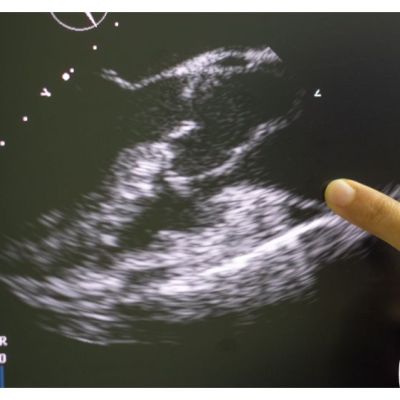

Valutazione ecocardiografica del Wall Motion Score Index

La valutazione della cinetica regionale e del Wall Motion Score Index (WMSI) è una metodologia diagnostica fondamentale per la comprensione della funzione cardiaca. Attraverso l’utilizzo di tecniche c…

Frazione di eiezione: come misurare la funzione sistolica globale

La frazione di eiezione è una misurazione della capacità di un ventricolo cardiaco di contrarsi e di espellere sangue ad ogni battito, ed è fondamentale per la valutazione della funzione sistolica glo…